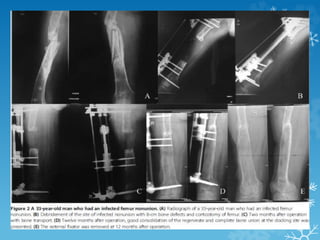

X-ray leg bones with knee joint anteroposterior and lateral views showing (a) Infected tibial

nonunion. Irregular bony ends. Had we

resected bone till achieving horizontal bony surfaces, it would have created a lot of

shortening (b) we gave compression at rate of one-fourth mm

twice a week to achieve compression but not cause an angular deviation. No bone grafting

done (c) Sound union, after ilizarov construct removal

X-ray leg boneswith knee joint anteroposterior and lateral views showing (a) Infected tibial nonunion. Irregular bony ends. Had we resected bone till achieving horizontal bony surfaces, it would have created a lot of shortening (b) we gave compression at rate of one-fourth mm twice a week to achieve compression but not cause an angular deviation. No bone grafting done (c) Sound union, after ilizarov construct removal